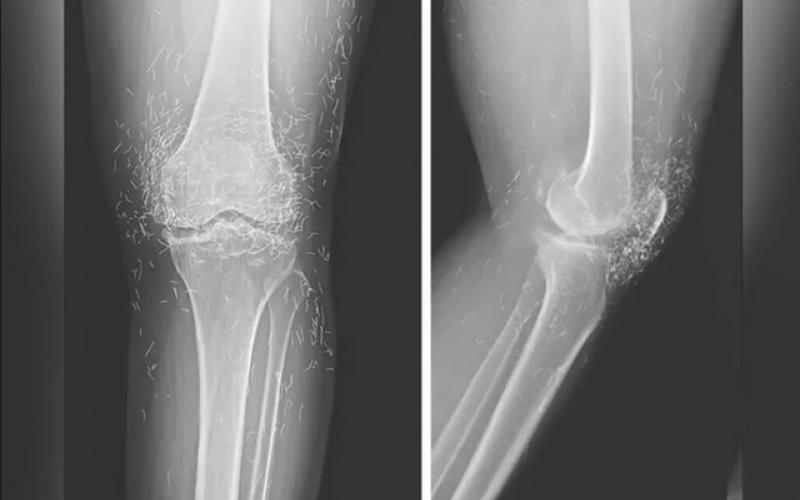

اما این روش هم نه‌تنها دردی از این زن دوا نکرد، بلکه زانودرد او را هم شدت بخشید. درنهایت او مجبور شد دوباره به بیمارستان مراجعه کند و پزشکان هنگام تصویربرداری از زانوها و دست‌های او متوجه صدها رشته‌ ریز و نازک از طلا در بافت‌های اطراف زانو و دست‌های این زن شدند.